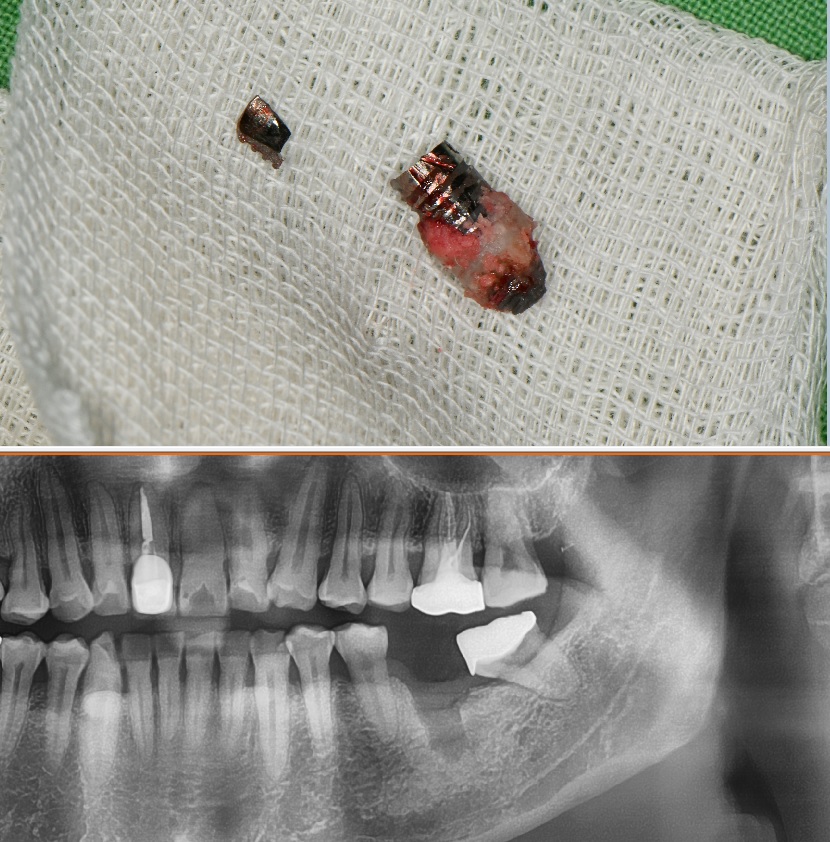

아래 사진을 비교해 보도록 하겠습니다

타치과에서 임플란트 시술을 받고 오신 분인데요

상악동 거상술을 못하는 치과에서

시술을 받다보니

임플란트가 굉장히 짧습니다

이런 임플란트는 문제가 될 소지가 높은데요

짧다고 무조건 나쁜건 아니지만 치아의 크기에 비하여 임플란트 비율이 너무 짧아서 그 기능이 충분하지 못할걸로 보입니다